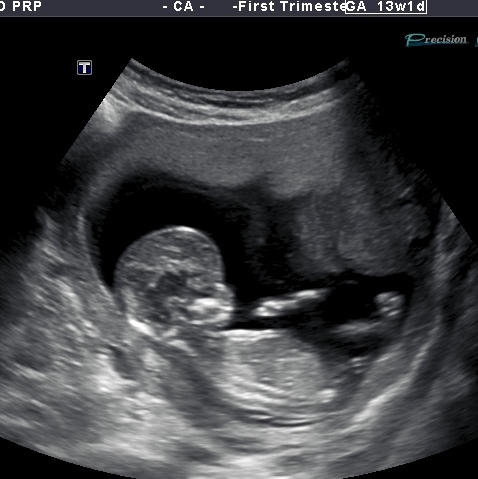

Elico's 13 week 1 day u/s pic

Hi there. I had my NT scan today and wow that bubba was hypo. The sonographer was struggling to get the correct info that was required of her. I was watching the scan closely and i saw nubs every so often and it was on an angle upward but not extremely vertical .... The pics i have of bub are just a handful of cute pics my lovely scanner put on a disk because hubby couldn't attend. i will get the whole lot of pics on monday where hopefully there will be more nub pics. So this is my only pic and im not even sure its a nub unless its a see through the leg one lol. Any advice appreciated.Attachment 12418